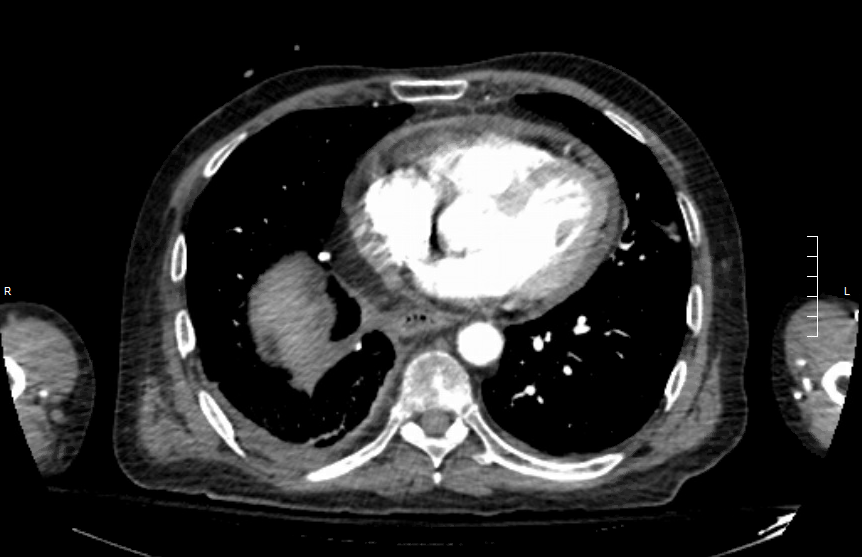

The patient’s history of cancer and associated high suspicion for pulmonary embolism prompted computed tomography (CT) pulmonary angiography, the results of which revealed an acute right upper lobe segmental pulmonary embolus (Figure 2). A small to moderate sized pericardial effusion was also noted (Figure 3).

Figure 3. CT pulmonary angiography showing moderate sized pericardial effusion.